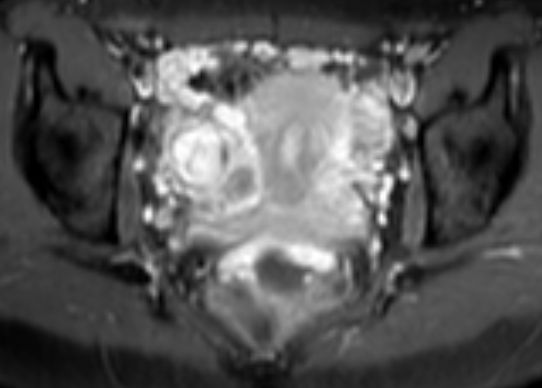

Pseudomyxoma peritonei 26-jährige Frau mit Tuboovarialabszess. Bei der Laparotomie fanden sich zahlreiche knotig-glasige Veränderungen im Peritoneum des Mittel- und Unterbauches sowie beidseits zystische Ovarien. Histologie: Pseudomyxoma peritonei (low grade). Dieses entsteht in den meisten Fällen auf dem Boden einer muzinösen Neoplasie des Gastrointestinaltraktes, insbesondere der Appendix. Die Ovarien dürften sekundär in den Prozess einbezogen sein.